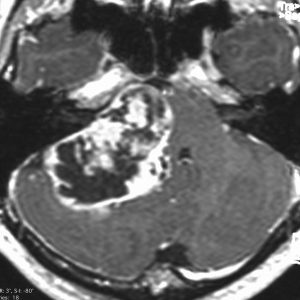

症例:延髄軟膜下 のもの subpial schwannoma in the medulla oblongata

40代男性です。咽せる,頚部痛という迷走神経症状で発症し,小脳失調がでてから腫瘍が発見されました。ある病院で第4脳室と脳槽内ののう胞性部分を摘出され,残存腫瘍摘出の目的で紹介されました。残った腫瘍は迷走神経根の腹側の延髄内部に食い込み,延髄軟膜下 subpial に主体がありました。nearly complete resectionをして経過を見ています。術後は嚥下障害が悪化したのですがかなり回復して,嗄声はなく自宅で食事をする日常生活にもどれました。